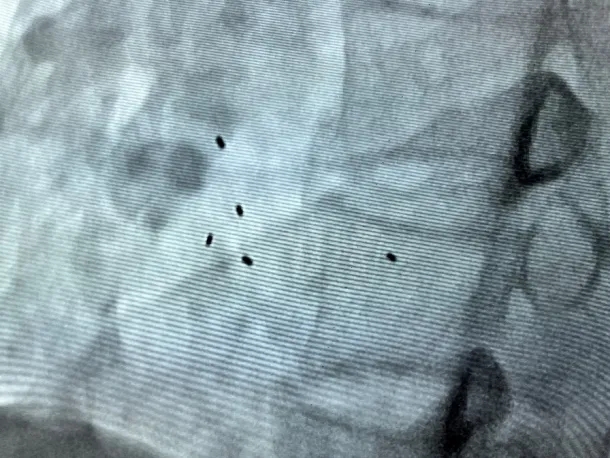

释放后评估

DSA下观察5个显影点聚集

整体移动不变形,封堵成功